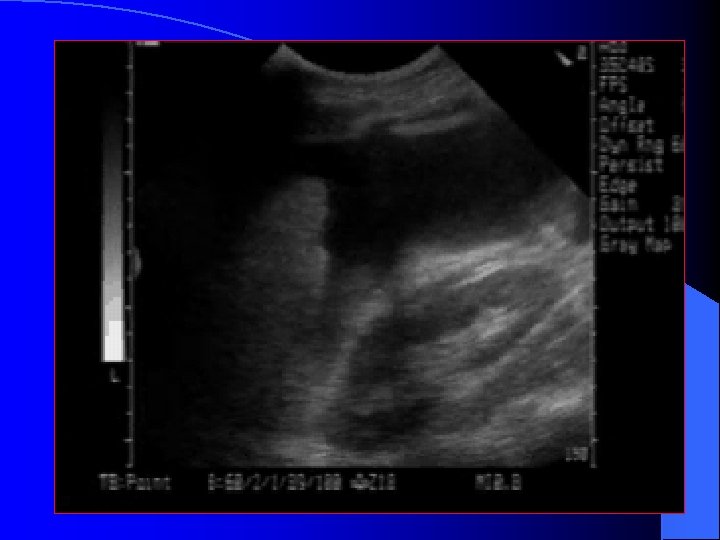

LUQ Scan Plane l More difficult – Acoustic window (spleen) is smaller than liver – Mild inspiration will optimize image – Bowel interference is common

LUQ Scan spleen * * * kidney * *Splenorenal fossa – a potential space

Normal Spleno -renal view Free fluid around spleen